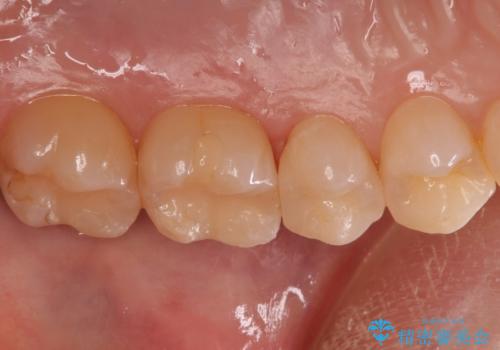

歯と歯の間の虫歯 セラミックインレーでの治療

- 検査の結果、歯と歯の間に虫歯が見つかった患者様です。

白く目立たないものでの治療をご希望されたため、セラミックインレーでの治療となりました。

- 左上5 セラミックインレー 77,000円費用は治療当時の料金となります

歯と歯の間は虫歯の好発部位です。

適合の良いセラミックインレーで修復することで見た目の綺麗さを保ったまま治療することができます。